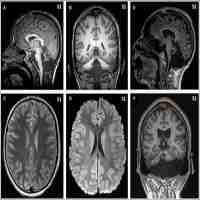

| Abstract | Phosphomannomutase 2 deficiency (PMM2-CDG) is the most frequent congenital disorder of glycosylation. PMM2-CDG patients develop chronic cerebellar atrophy as a neurological hallmark. However, other acute neurological phenomena such as stroke-like episodes (SLE), epilepsy, migraine, and cerebrovascular events, may also occur, and they are frequently the cause of disability and impaired quality of life. Among these, SLE are among the most stressful situations for families and doctors, as their risk factors are not known, their underlying pathomechanisms remain undiscovered, and clinical guidelines for diagnosis, prevention, and treatment are lacking. In this paper, the recent SLE experiences of two PMM2-CDG patients are examined to provide clinical clues to help improve diagnosis through a clinical constellation of symptoms and a clinical definition, but also to support a neuroelectrical hypothesis as an underlying mechanism. An up-to-date literature review will help to identify evidence-based and non-evidence-based management recommendations. Presently neuropediatricians and neurologists are not capable of diagnosing stroke-like episodes in an unequivocal way, so there is still a need to perform invasive studies (to rule out other acute diseases) that may, in the end, prove unnecessary or even harmful. However, reaching a correct and early diagnosis would lead not only to avoidance of invasive tests but also to better recognition, management, and understanding of the disease itself. There is a great need for understanding of SLE that may ultimately be very informative for the detection of patients at risk, and the future development of preventive and management measures. |